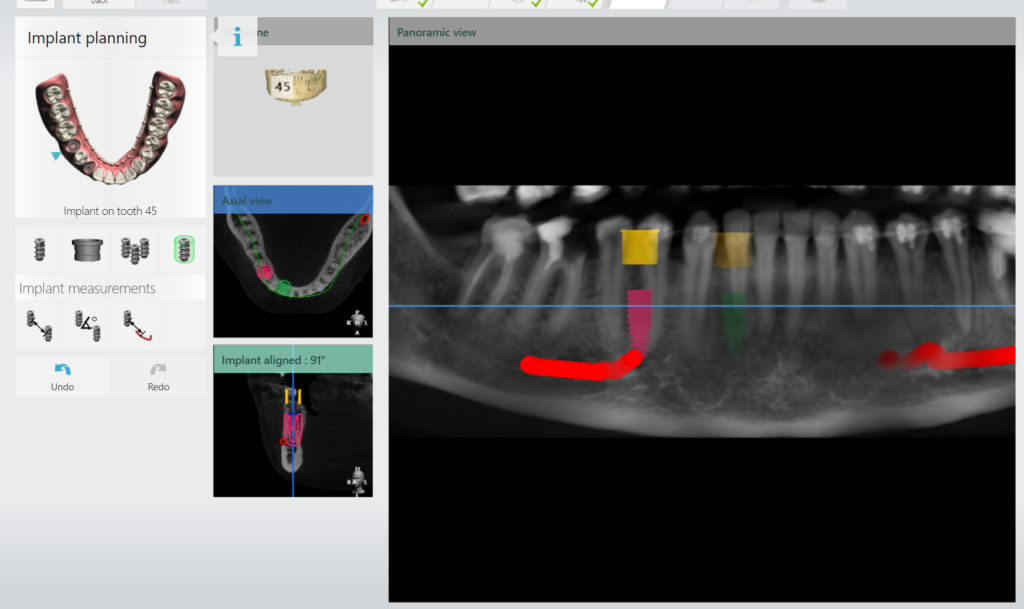

След това така създадения отпечатък на пациента под формата на STL файл се изпраща към специализиран софтуер за изработка на хирургичен водач. В нашата клиника използваме най-съвременния имплантологичен софтуер на 3Shape.

При самата обработка на изображенията д-р Парушева може да види с точност да микрон къде трябва да бъде поставен импланта и под какъв ъгъл. Не само това, но тя има възможността да види какво е състоянието на костта, къде се намира нервът на долната челюст, синусите, колко е дебела костта и да го позиционира така, че да бъде правилно поставен, без да се очакват допълнителни проблеми:

Софтуерът показва в червено нервът на долната челюст и, че имплантът не може да бъде поставен толкова близо до него: